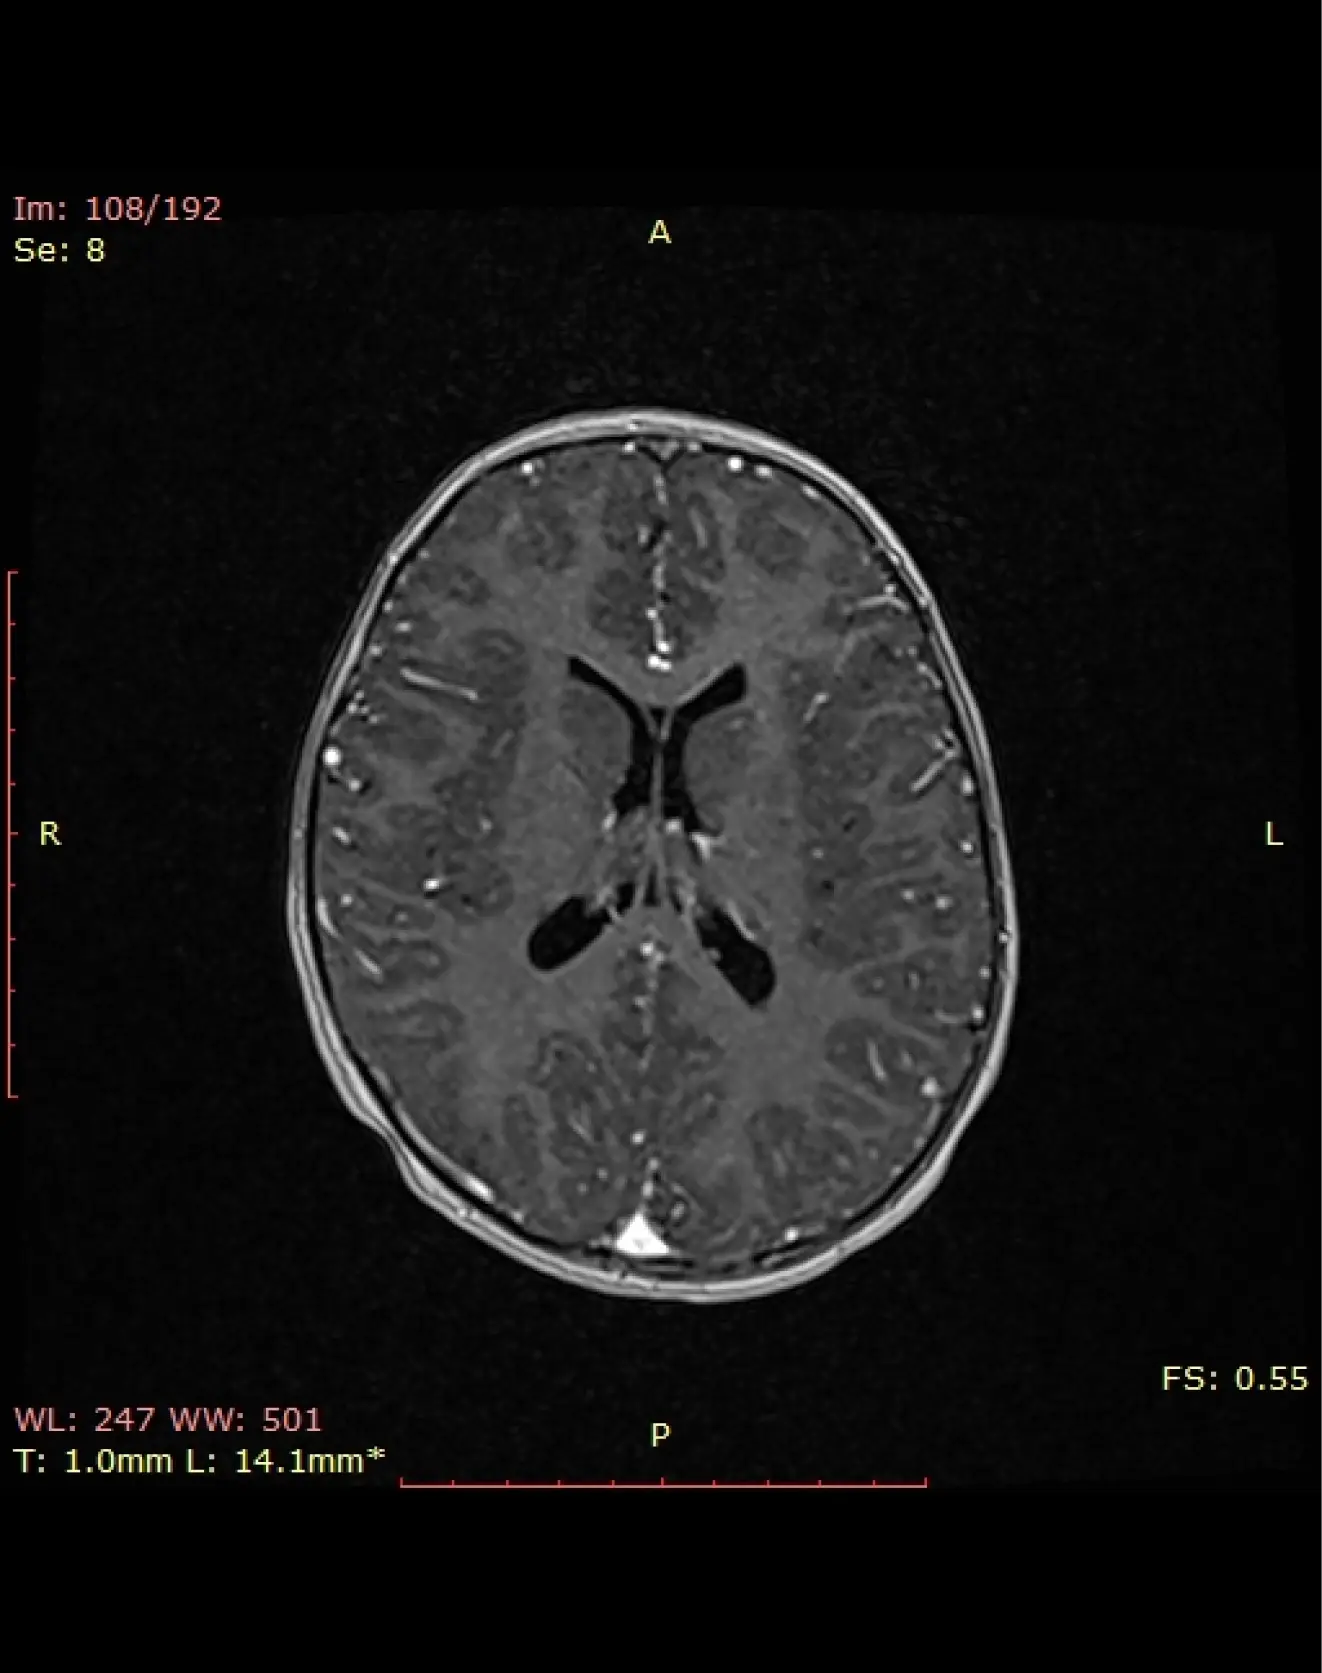

МРТ головного мозга в эпилептическом режиме

Специализированное исследование, предназначенное для выявления структурных изменений, связанных с эпилепсией.